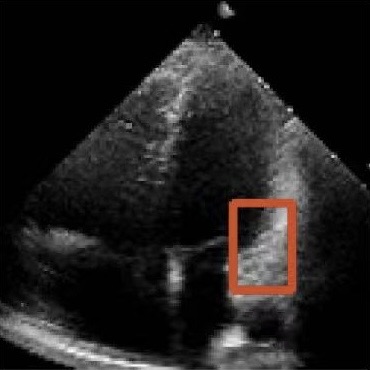

Challenges in Echocardiography Segmentation 超声心动图视频分割面临的挑战

Echocardiography segmentation faces several challenges such as low contrast, speckle noise, and signal dropout. 超声心动图视频分割面临着诸如低对比度、斑点噪声和信号丢失等多重挑战。

Shape

(c)

Scale

(d)

Cycle

(e)

Dropout

(f)

Figure 2. Illustrative challenges for echocardiography video segmentation: (a) speckle noise, (b) indistinct or blurred contours, and (c-f) the substantial changes in the target’s shape and scale throughout the cardiac cycle. 图 2. 超声心动图视频分割面临的典型挑战:(a) 斑点噪声,(b) 轮廓不清或模糊,以及 (c-f) 在整个心动周期中目标的形状和尺度发生的显著变化。